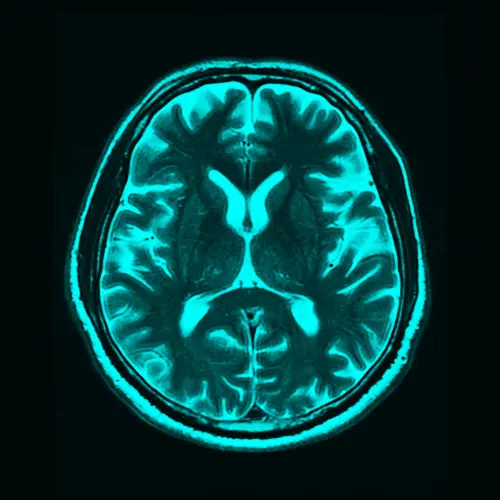

Localization for imaging and diagnostic platforms

From MRI and CT user interfaces to diagnostic reporting software, we translate every field, button, and message with medical‑grade clarity. Our translators coordinate with subject‑matter experts (SMEs) to validate terms for radiology and pathology contexts, ensuring clinical credibility across screen and paper.